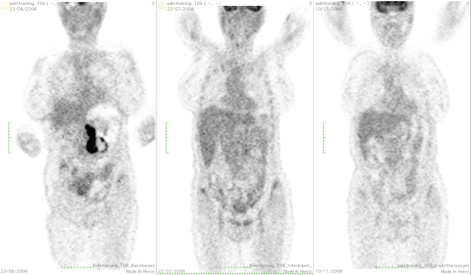

In 2009–2010 three private cyclotrons were installed in Buenos Aires that led to a significant increase of FDG supply. At present, more than 25 PET scanners operate in the country. Once the new scanners were installed, the technical skill of the scanner operators, as well as the medical experience of nuclear medicine physicians grew, and this facility expanded in Argentina. The production and supply of FDG became reliable and sustained, and other radiopharmaceuticals were gradually introduced and produced, such as 18F-choline, 18F-DOPA, 68Ga-DOTA-PePeptide, 68Ga-PSMA 18F-NAF, 11C-PIB, and others which are under development at this writing in October 2021. An example of the use of PET/CT before, during, and at the end of treatment of an advanced HL is presented in Figure 1.

Fig 1

Figure 1. PET/CT. Patient with advanced HL having performed PET/CT at baseline (left), after two cycles of ABVD (center) and after further 4 cycles of esc-BEACOPP (right). The mediastinal lesion, even if decreased in both dimension and uptake show a residual uptake higher than the liver (partial metabolic response, Deauville score 4). Consequently, the patient was treated with esc-BEACOPP with no residual lesion at the end of treatment (complete metabolic response, Deauville score 1).